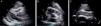

Caso clínicoDoente do sexo masculino, 51 anos de idade, raça negra, desportista habitual, sem antecedentes pessoais patológicos relevantes. Recorreu ao serviço de urgência por quadro clínico, com cerca de uma semana de evolução, de cansaço, de agravamento progressivo, dor precordial tipo picada ocasional, aumento do volume abdominal, anorexia e intolerância alimentar, com vários episódios de vómitos. Três dias antes do internamento teve um episódio de síncope e notou o aparecimento de engorgitamento jugular significativo. Negou febre, calafrios, tosse, expetoração, perda ponderal. À observação apresentava PA 118/78mmHg, FC 98bpm, estava apirético, dispneico, com engorgitamento jugular, tons cardíacos apagados, sem edema periférico. O eletrocardiograma (ECG) mostrava ritmo sinusal, com baixa voltagem dos QRS nas derivações clássicas e dos membros e padrão S1Q3T3 (Figura 1). Analiticamente destacava‐se discreta elevação de parâmetros inflamatórios (leucócitos 11,6x109/L, PCR 3,9mg/dL), marcada elevação dos D‐dímeros (5.153ng/mL), Hb 13,3g/dL, creatinina 1,3mg/dL e marcadores de necrose miocárdica negativos. Realizou angio‐TC de tórax que excluiu tromboembolismo pulmonar, mas revelou volumoso derrame pericárdico e pleural direito. O ecocardiograma mostrou volumoso derrame pericárdico circunferencial de características não límpidas, com dimensão máxima de 32mm e colapso parcial das cavidades direitas (Figura 2). Para fins diagnósticos e terapêuticos, foi realizada pericardiocentese evacuadora sob controlo fluoroscópico, com drenagem de líquido sero‐hemático (4000cc no total). O estudo citoquímico revelou líquido pericárdico com características de exsudado, com níveis de ADA normais. O exame citológico não revelou células neoplásicas e o exame microbiológico direto e cultural foi negativo, nomeadamente para micobactérias. Foram pesquisados vários marcadores de doenças autoimunes (ANA, fator reumatoide, anticardiolipina, anti‐β2 glicoproteína, níveis de C3 e C4) e de doenças hemato‐oncológicas (CEA, CA 19,9, PSA, α‐fetoproteina, β‐2 microglobulina, esfregaço de sangue periférico), não se obtendo nenhum valor com contribuição positiva para o diagnóstico. A pesquisa de anticorpos virais (echovirus, Coxsackie, adenovírus, influenza A e B, VIH, VHB, VHC) foi negativa ou não sugestiva de infeção recente. A TC toraco‐abdomino‐pélvica apenas revelou polisserosite, não mostrando nomeadamente adenopatias ou outras massas suspeitas. Posteriormente, obteve‐se positividade no doseamento do Interferon‐γ release assay (IGRA), pelo que se assumiu o diagnóstico de pericardite tuberculosa e o doente iniciou terapêutica com tuberculostáticos.

Imagem de ecocardiografia bidimensional transtorácica em plano (A) paraesternal longo eixo, (B) paraesternal curto eixo e (C) subcostal, mostrando volumoso derrame pericárdico circunferencial de características não límpidas, com colapso parcial das cavidades direitas. DP: derrame pericárdico; VD: ventrículo direito; VE: ventrículo esquerdo.